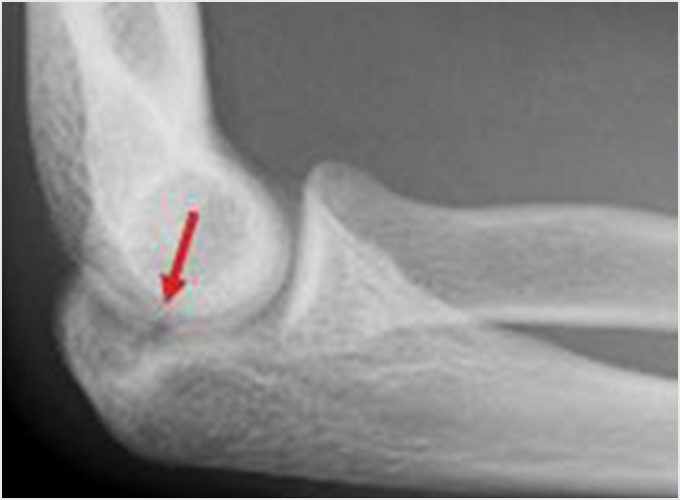

離断性骨軟骨炎(上腕骨小頭障害)

野球肘で最も重症になる障がいの1つです。ひどくなると関節軟骨の一部がはがれて関節ネズミとなったり、肘が変形して動きが悪くなったりします。初期に発見されれば投球禁止で治り、手術はしなくてもすむ場合が多いのですが、末期になると手術が必要となり、手術をしても肘の動きの制限や変形が残ってしまうこともあります。10歳前後で発症することが多いのですが、初期には自覚症状がないことが多く、13-17歳ごろにグラグラになった軟骨がはがれて痛みが出て初めて医療機関を受診されることもよくあります。 手術となった場合には骨の成長の度合い、病変の進行具合、病変の大きさなどにより手術方法が変わります。軟骨が安定している場合には軟骨を固定する手術を行う場合が多いです。軟骨がはがれている場合、病変が小さければ関節鏡を用いてはがれた、あるははがれかけている軟骨を摘出します(図4a)。病変の直径が1㎝以上であれば切開手術で膝の軟骨を病変部に移植します(図4b)。 最近全国各地で少年野球検診が行われるようになりましたが、一番の目的は離断性骨軟骨炎を早期に発見し、重症になる前に治療を行うことなのです。平成28年から多くの医師、理学療法士の協力により名古屋でも行われるようになりました。私も検診に参加し、エコーでのチェックを担当しました。およそ100人に1-2人の割合で発見されました。